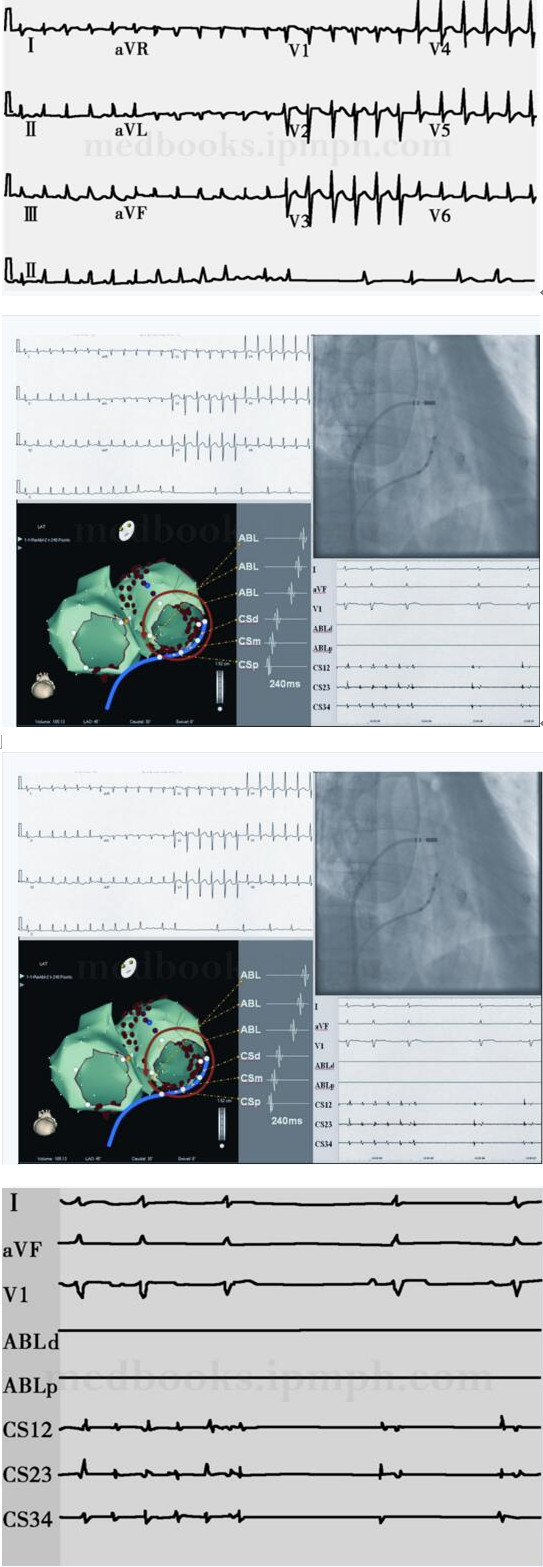

消融中止房扑、房颤转复窦性心律已经是慢性房颤苛刻的消融终点了,心房快速刺激又诱发出另一种规律房性心动过速,即第2个房扑,体表心电图形态与第1个房扑极其相似(图84‐6A),首先被认为是CTI传导恢复所致的CTI依赖的右房房扑,于是便在CTI处进行消融,与初次中止第1个房扑不同,消融5分钟尚不能中止房扑(原来在相同部位消融共1.5分钟即中止并且阻断CTI),右房房扑有疑问。因此采用消融导管沿二尖瓣环快速标测一周,提示为绕二尖瓣环折返房扑(图84‐6B),拖带是判断折返及折返关键部位的重要刺激技术,但因其可改变折返环路使问题变得更加复杂,在通过电解剖三维标测技术可直视折返环路时代很多人并不愿意进行拖带刺激。

图84‐6 绕二尖瓣环折返左房房扑(第2个房扑)

A图为快速心房刺激诱发的第2个房扑12导联ECG;B冠状静脉窦激动顺序由近及远(CS),用标测消融导管标测(ABL)显示激动绕二尖瓣环逆钟向折返,诊断为绕二尖瓣环折返的左房房扑;C为消融中止该房扑的X光影像(RAO30°),可见消融电极位于间隔顶部左房侧相对接近二尖瓣环处;D为消融中止该房扑心电记录

绕二尖瓣环折返左房房扑的消融:因为已在二尖瓣环峡部对CFAE进行过较为激进的消融,并且仅仅经心内膜途径较难阻断二尖瓣环峡部,因此首先在左房间隔中上部近二尖瓣环处进行消融,奇怪之处是虽然为围绕二尖瓣环折返的规律心动过速,消融导管却在图84‐7中黄色球状点处记录到了典型的CFAE(图84‐7白框放大部分),在此消融中止左房房扑(图84‐6C、84‐6D)。第1、2两个房扑体表心电图类似,但是机制迥异,解释详见图84‐8。

图84‐7 消融中止第2个房扑的三维影像位置及靶点图

左侧为左心房CARTO解剖构型(前后位),细红圈代表二尖瓣环位置,黄色球状点代表图6C X光影像中消融电极在CARTO影像上的对应位置,在该点记录的局部电图振幅低、频率快(图中白方框放大部分),为典型的CFAE,图右下角可见消融过程中房扑中止

图84‐8 不同房扑相似体表心电图的机制

左图为CTI依赖房扑(第1个房扑),右心房激动绕三尖瓣环逆钟向旋转,左心房被动激动经左后间隔起始,然后沿房间隔向上传导,同时沿下壁向左外侧传导;右图为绕二尖瓣环折返的左房房扑(第2个房扑),左房绕二尖瓣环逆钟向激动。与左图第1个房扑有些相似,右房经间隔部被动激动,因CTI已经阻断,右心房激动实际上与CTI依赖的房扑类似,绕三尖瓣环逆钟向传导。因此两种房扑机制上区别极大,但体表心电图表现相似

图84‐9 快速心房刺激不能诱发任何房性心动过速

快速心房刺激不能诱发任何房性心动过速作为房颤消融终点不仅在阵发房颤,而且在持续房颤也是可行的

之后,快速心房刺激不能诱发任何房性心动过速(图84‐9)。对于慢性房颤实现消融中止的终点已经使工作变得有些艰辛,进一步追求快速心房刺激不能诱发更增大了消融难度,因此有学者认为激进诱发可能是多余的。我们追求此消融终点的原因是根据我们既往消融和随访结果,消融后诱发持续性房性心动过速而未消融者,多数也是以后复发的心动过速。